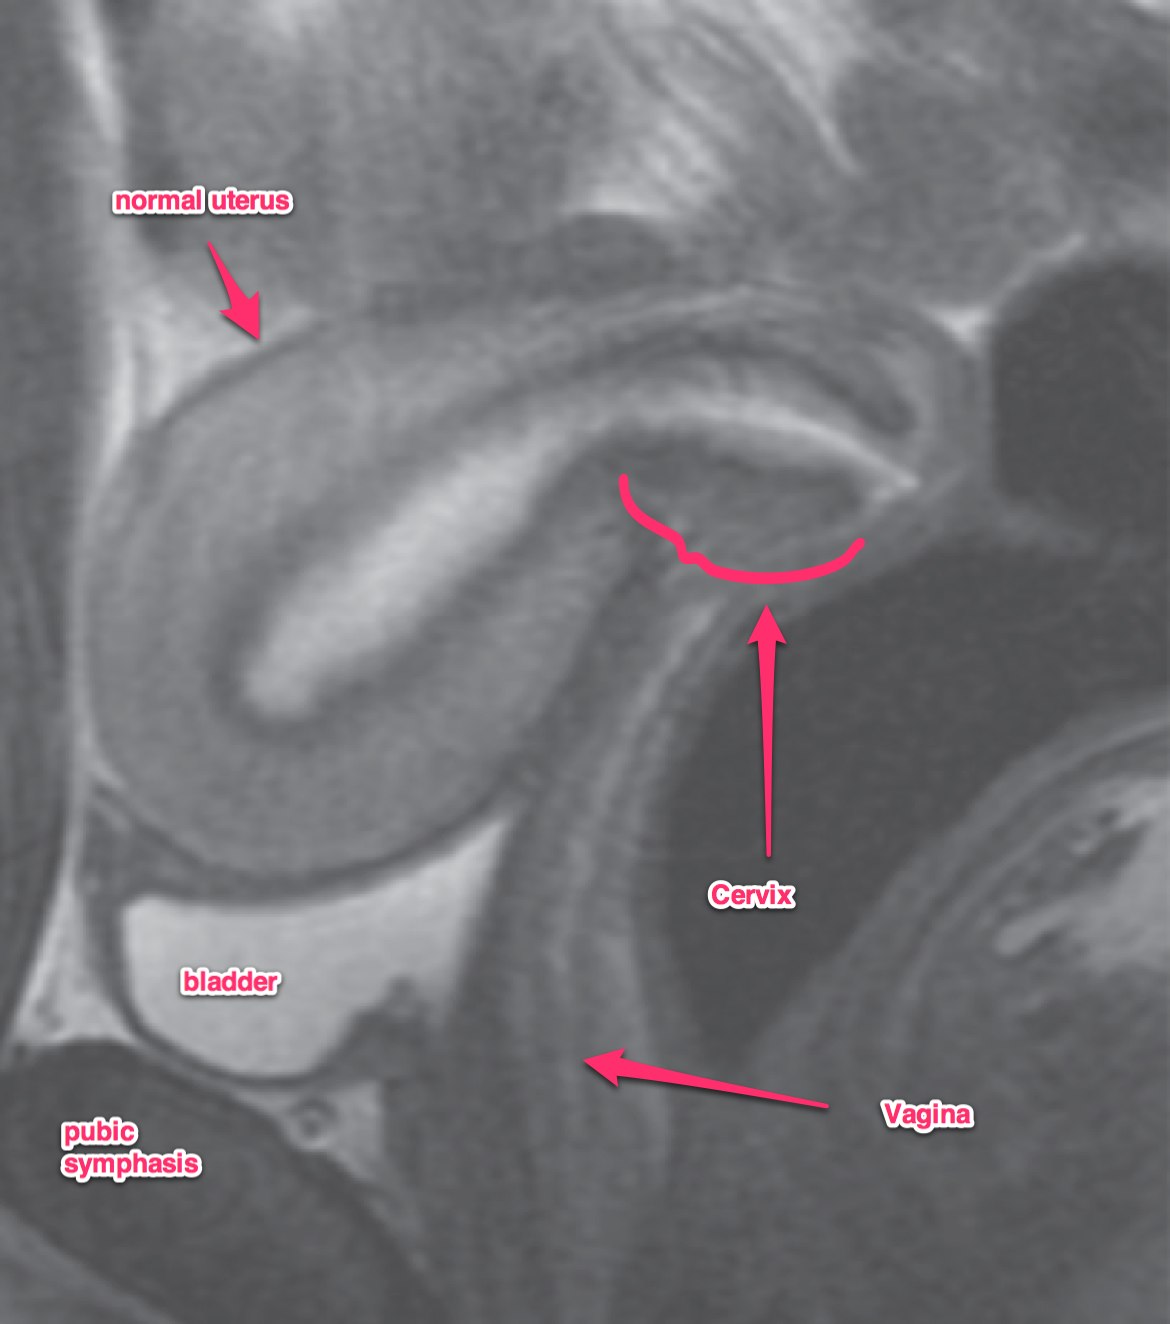

A transvaginal ultrasound should be obtained. In post-menopausal women, the expected endometrial thickness is < 4 mm. In pre-menopausal women, the thickness varies with the menstrual cycle. MRI is useful in identifying suspicious hyperplasia. If a thickened myometrium is visible on contrast enhanced CT, it is likely there is > 50% myometrial invasion. Cervical stromal invasion is seen on CT as an enlarged cervix, > 3 cm, heterogeneous stroma with low attenuation. Parametrial invasion is seen by loss of fat in the periureteral region, and fat plane near the pelvic sidewall.

Dynamic contrast enhanced MRI is optimal for MRI studies with accuracy of 85% or better. If there is a clear junctional zone between the tumor and the myometrium, the disease is most likely limited to the myometrium. MRI can also determine depth of cervical stromal invasion.